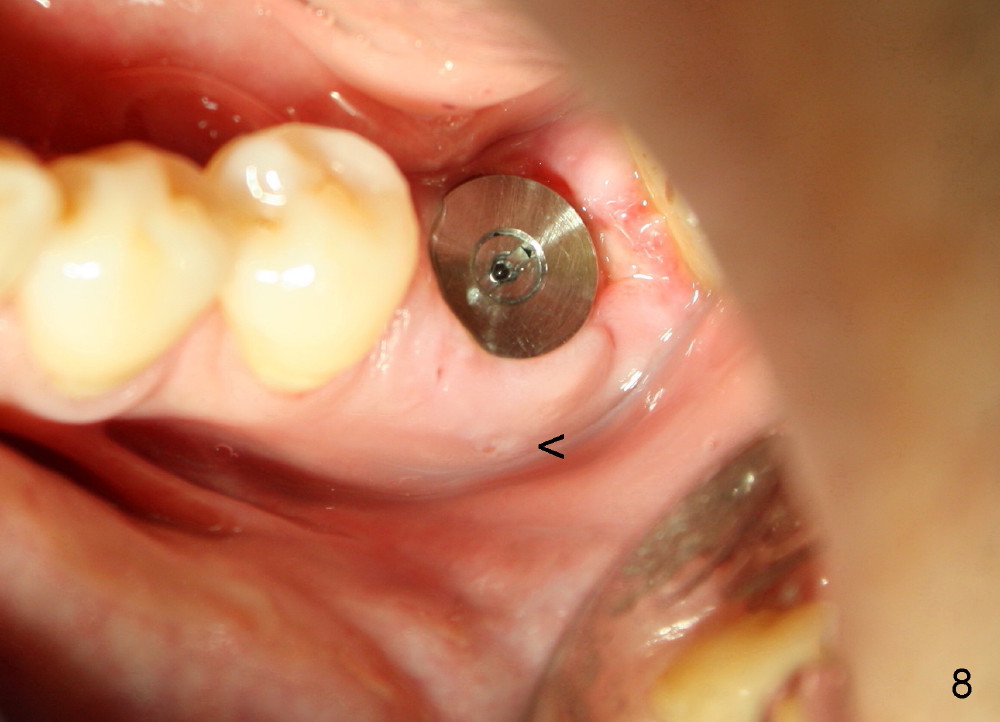

A 41-year-old man has discomfort in the lower left 1st molar. Exam shows swelling and a fistula in the mesiobuccal gingiva (Fig.1 >) and large radiolucency around the mesial root (Fig.2 *). After extraction and thorough debridement, osteotomy is initiated in the mesial socket, but the upper portion of the reamer (Fig.3 R, 2.5 mm) is placed in the middle of the edentulous space. By the time 5 mm reamer is removed, the osteotomy (Fig.4 O) forms mainly in the mesial socket with the septum (S) deviated to the distal socket. A 7x17 mm tap is placed with stability (Fig.5 T). An implant with the same dimension is placed with insertion torque more than 60 Ncm (Fig.6 I). With the large implant, two proximal sutures are able to close the remaining socket gaps (Fig.7). The swelling and fistula disappears and the gingiva tightly surrounds the implant in 1 week postop (Fig.8).

There is a thick gingival band buccal to the implant 7 months postop (Fig.9 *). Osteointegration occurs (Fig.10). The most unexpected finding is the formation of the papillae (Fig.11 *) when the permanent crown is seated. The cosmetic result is due to immediate placement of the large implant. Delayed implant usually cannot achieve this type of outcome.